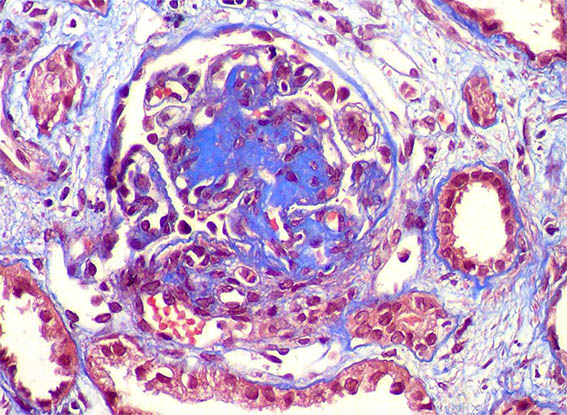

A 33-year-old man presented with pedal edema, persistent proteinuria and hypertension. Her past and family histories were unremarkable. Her blood pressure was 160/100 mm Hg. Physical examination revealed pedal and facial edema, without other alterations. Laboratory tests showed proteinuria of 4.7g/24 h, serum creatinine 1,0 mg/dL, microhematuria, normal serum complement levels, ANA negative; HIV, hepatitis B and C viral infections were negative. Ultrasound of the abdomen showed normal sized kidneys.

Kidney biopsy was performed. Look at the images.

Figure 4. Masson's trichrome stain, X400.